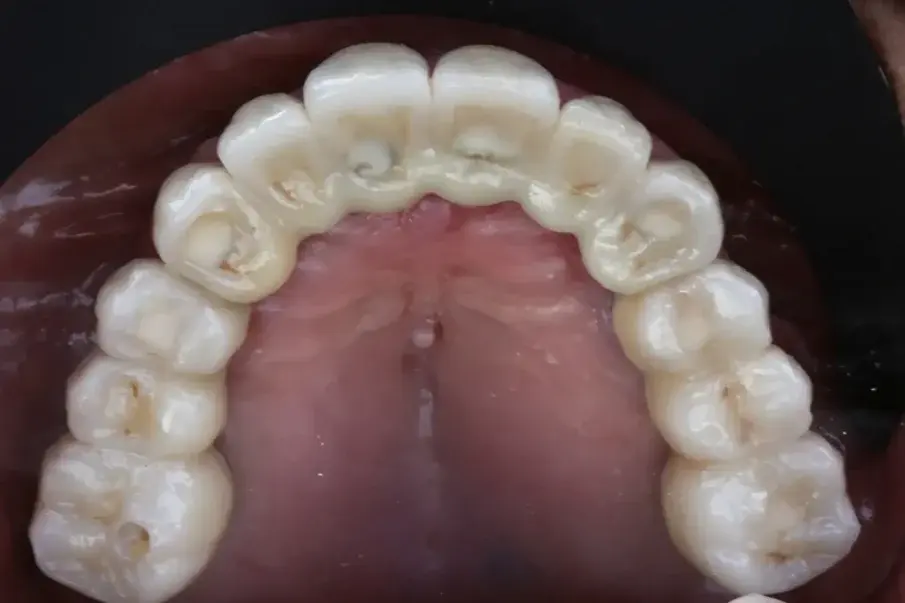

Фиг. 20: Окончателна протеза при едногодишното проследяване, оклузален изглед.